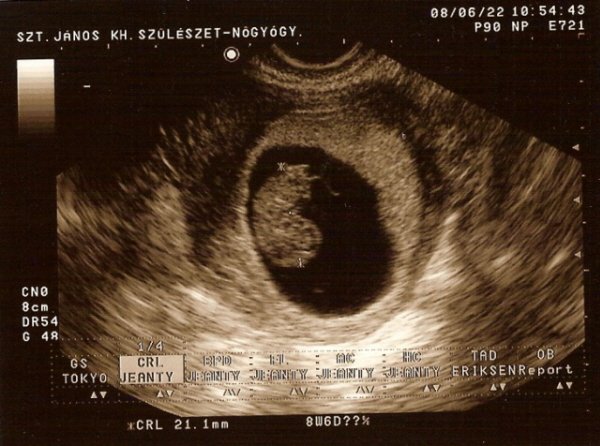

Addig felteszem Babó eddigi két sztárfotóját Nektek!!!

a>